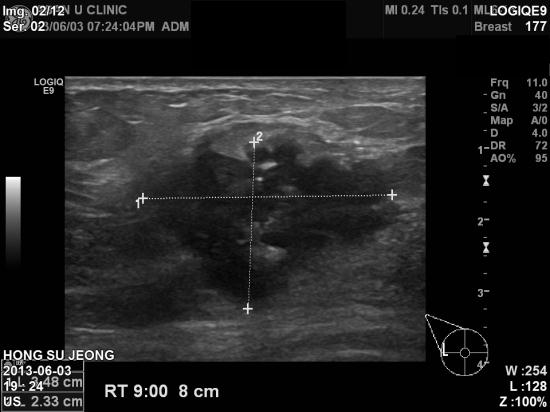

아산유외과 개원 후 15번째 유방암 진단.

9년전 상피내암, 즉 0기암으로 수술후 2년동안 괜찮아보여

정기검진없이 지내시던 분으로

오랜만에 의료보험공단의 건강검진으로 이상소견이 나와

과거 우측 수술부위와

우측 겨드랑이에 유방암이 진단 되셨습니다.

방심은 절대 금물입니다.